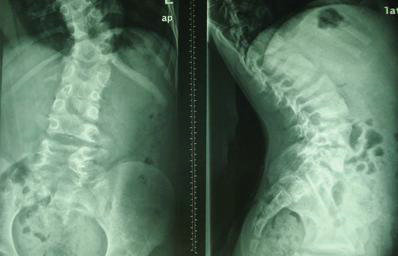

(图:入院时章先生X光片)

在详细的检查之后确定为强直性脊柱炎,结合章先生的病情和身体状况,崔丽主任为他制定了疗程短、见效快的治疗计划。